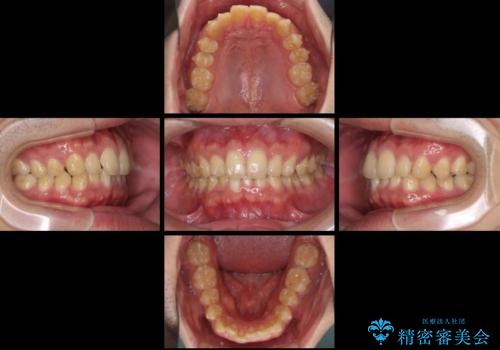

- 上下前歯のデコボコと下の前歯が隠れるほどの深い咬み合わせを気にして来院された患者様です。

インビザラインによる上下歯列の拡大と、IPR(歯と歯の間を削る)にるスペースの獲得により、口元のデコボコとディープバイトを改善することとしました。

デコボコがなくなったことで日頃の清掃が行いやすくなり、深い咬み合わせが改善したことで、食いしばりによる顎の負担も軽減されました。